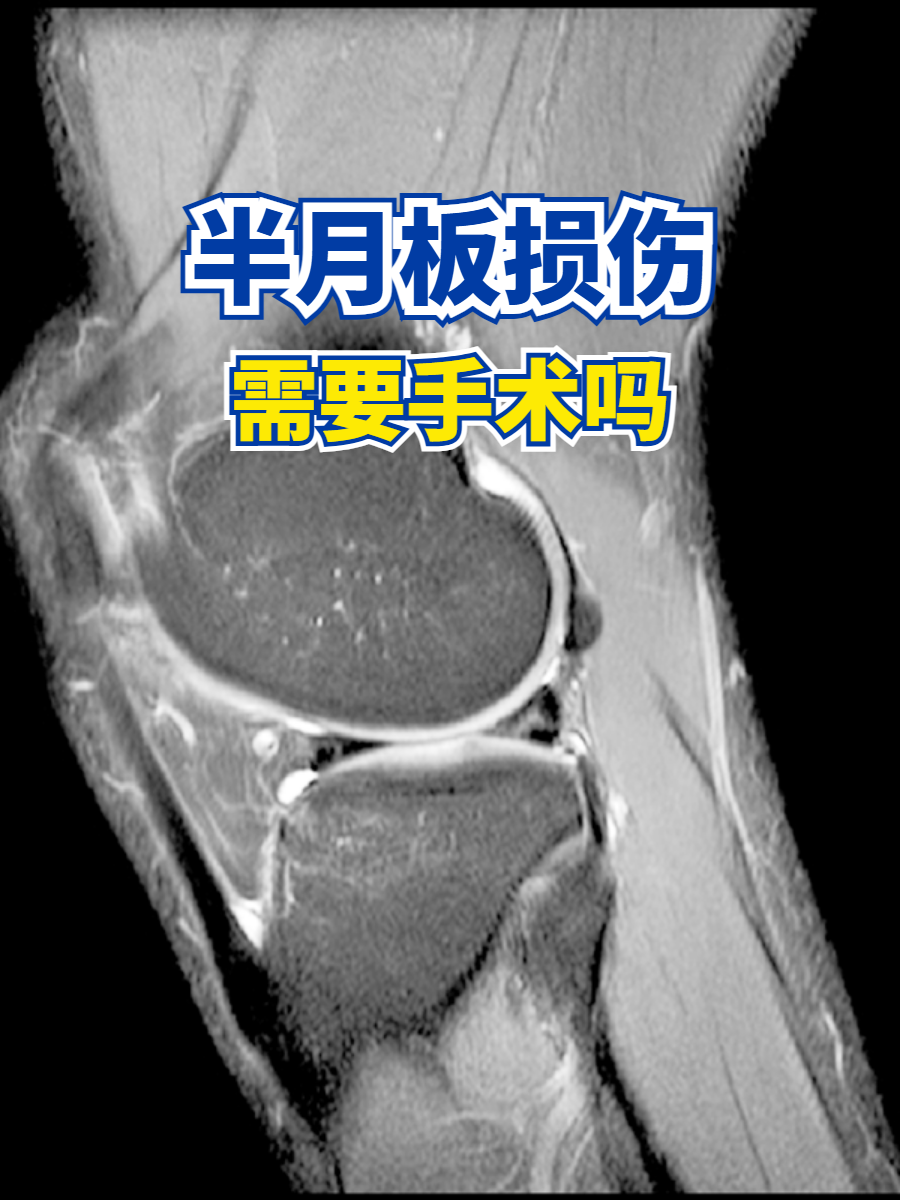

半月板损伤需要手术吗